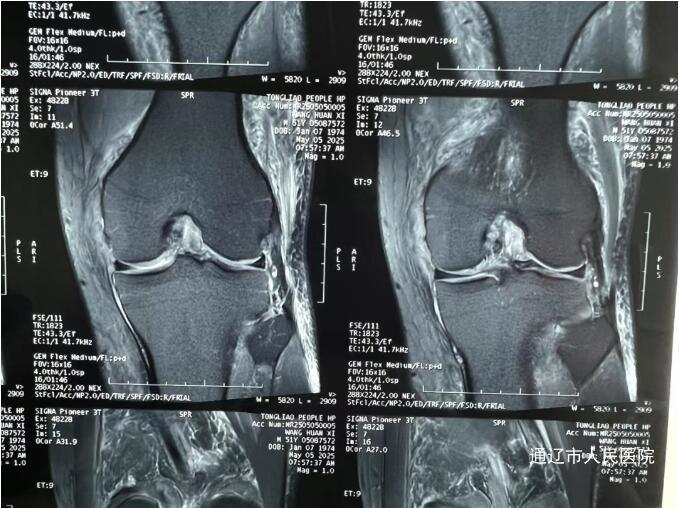

术前

(前交叉韧带损伤MRI图像)